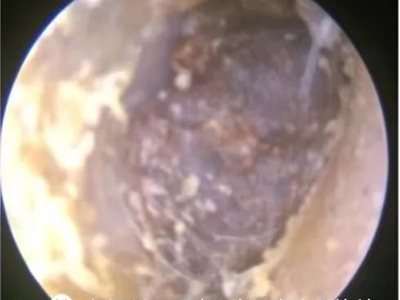

外耳道耵聍栓塞耳内有多个膜状物图

外耳道耵聍栓塞患者外耳道软骨部皮肤耵聍腺、皮脂腺不断分泌出黏性物质,均匀分布在外耳道处,干燥后形成黄白色鳞屑,并不断脱落。